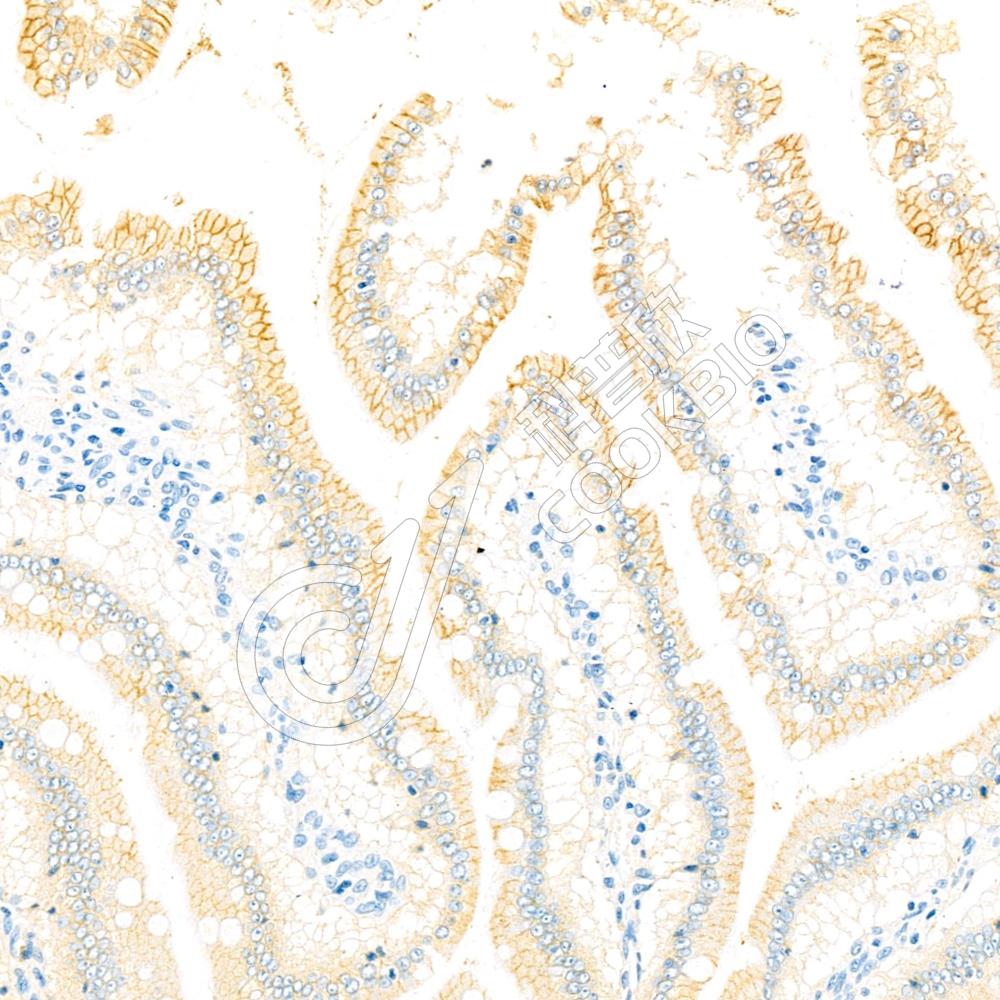

IHC检测PMCA1蛋白(货号 K1335766).

样品: 大鼠小肠, 4%多聚甲醛 (货号KSG1101) 固定12-24小时.

抗原修复: 柠檬酸抗原修复液(干粉, pH 6.0) (KSG1201), 98℃, 20分钟.

—抗: 1: 1300稀释, 4℃ 孵育过夜.

二抗: S-vision免疫组化多聚二抗(山羊抗兔),即用型 (货号KB3906), 室温孵育20分钟.